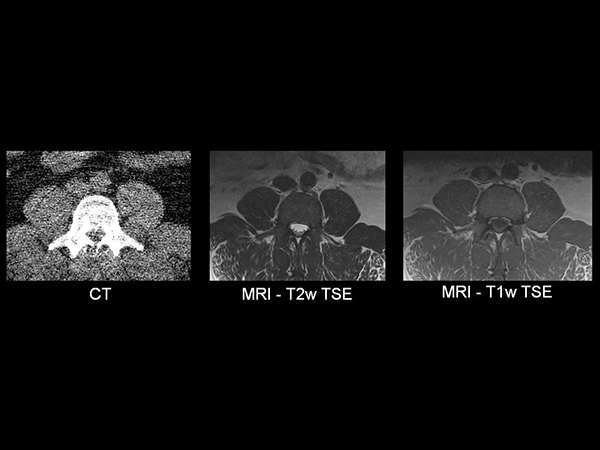

32- year old male patient, 180 kg, with back pain. Was first examined on CT but quality was not sufficient for diagnosis. MRI gave excellent images. Diagnosis: small protrusion of the disc L5/S1, no meningioma.